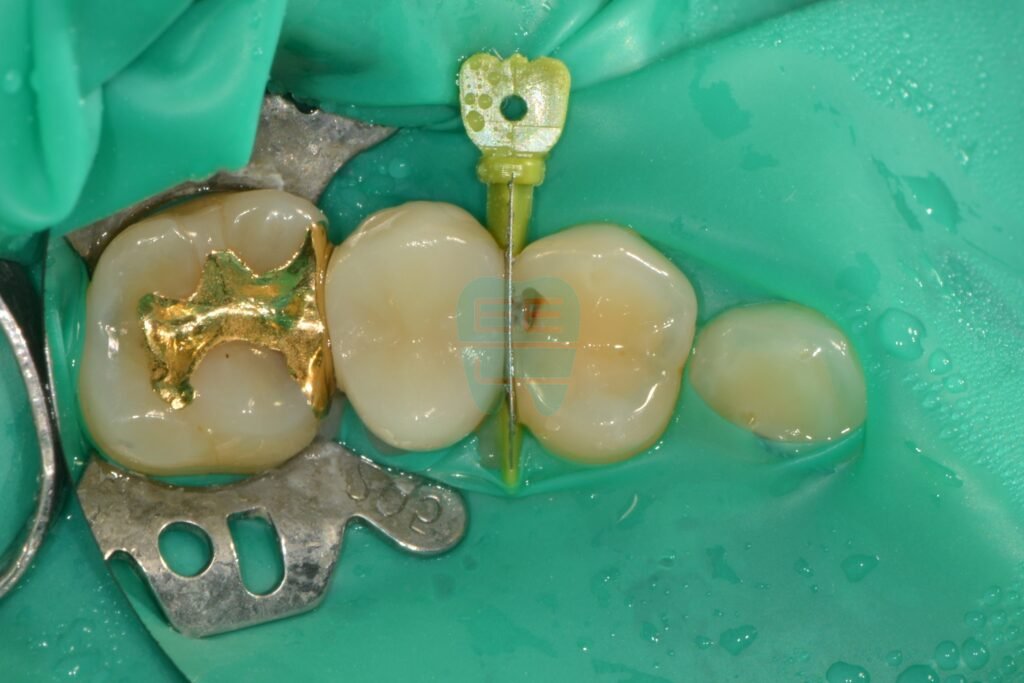

2. Precision Matrix Placement (Matrix System)

The key to interproximal caries treatment lies in how naturally the missing side wall is restored. A careless filling creates gaps between teeth, leading to more food impaction and eventually gum inflammation.

We use a specially contoured band (matrix) that matches the tooth's curvature, secured with a Garrison Strata-G ring system.

Matrix band and ring system placed for interproximal resin build-up

Interproximal resin build-up in progress

This step is critical. The contact point — where adjacent teeth press firmly together — must be perfectly recreated so that food no longer gets trapped after treatment.